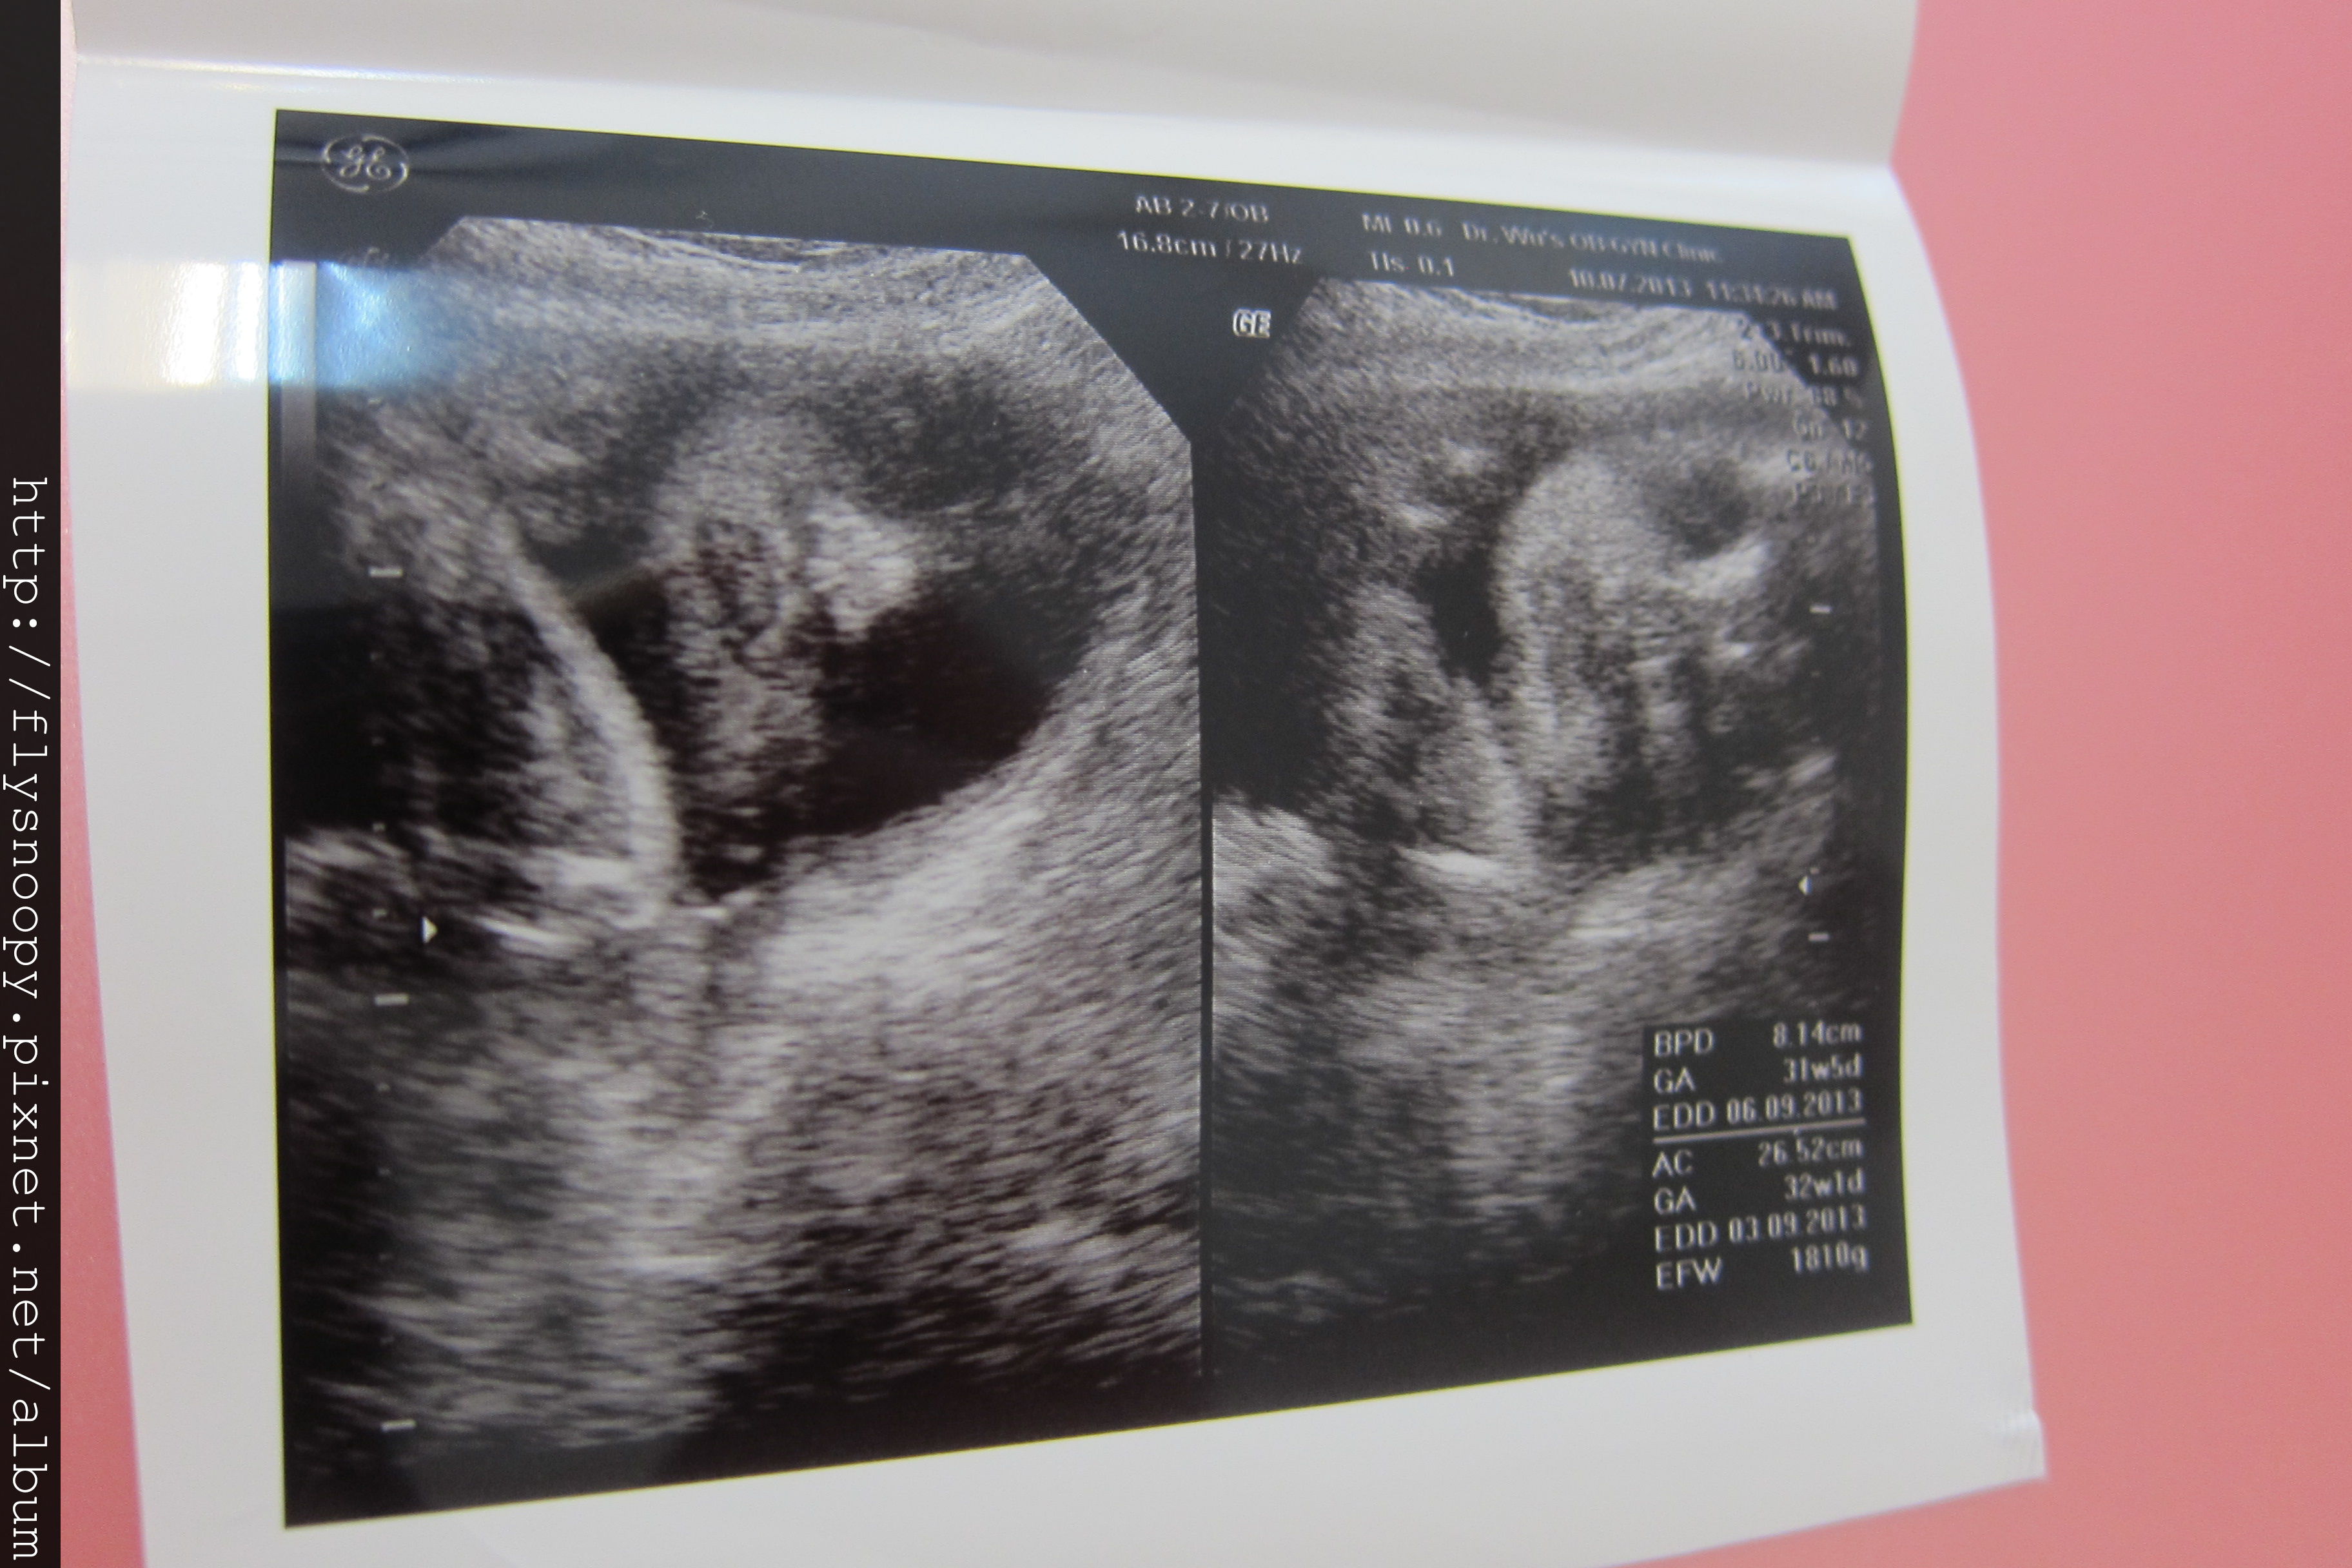

第八次產檢記錄

體重:63.5

血壓:105/67

尿糖、尿蛋白:正常

EFW:2003(突破2000囉~~~~~)